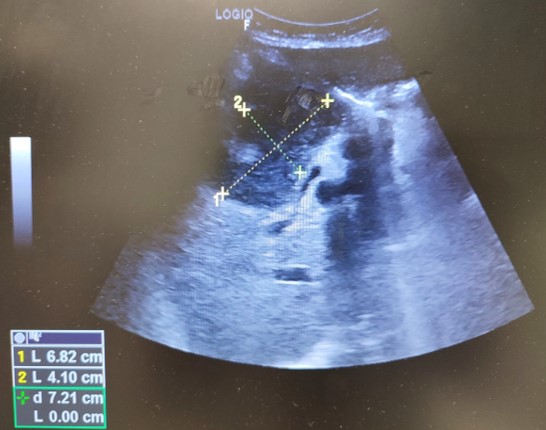

Ecografía abdominal, en la que se identifica masa hepática hipoecoica, heterogénea, de márgenes parcialmente lobulados, de 6.8 cm de diámetro, en región vesicular, con aumento de vascularización y dilatación de via biliar intrahepática. Impresiona de conglomerados adenopáticos en hilio hepático. Páncreas, bazo y riñones normales. No líquido libre intraabdominal.